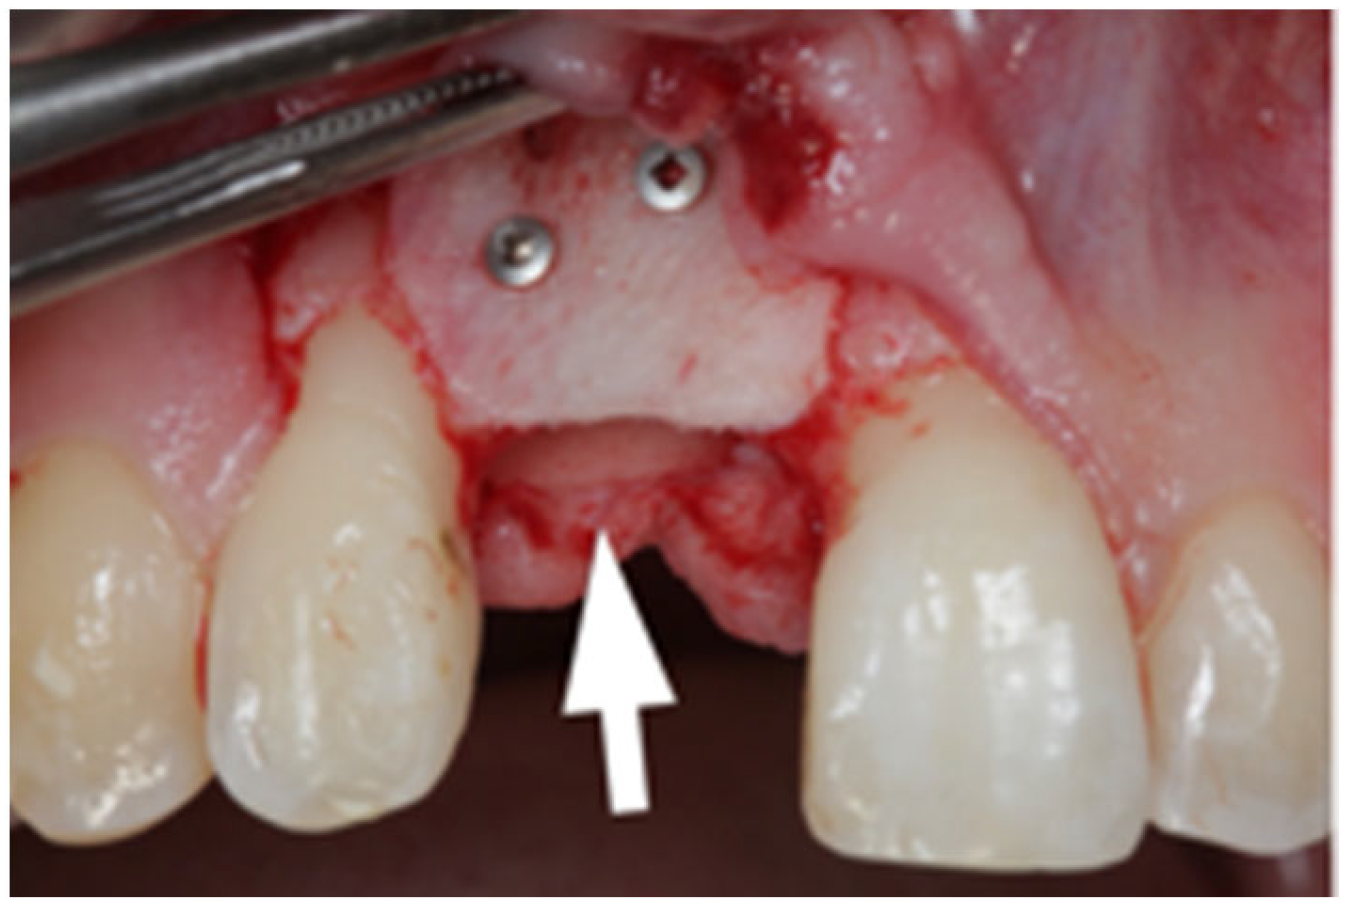

2.1. Surgical Technique